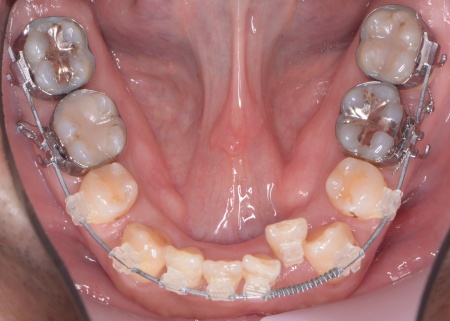

①抜歯をしてから歯並びを整える「抜歯矯正」 今回のケースでは、左上下の奥歯各1本(第3大臼歯)、右下の奥歯1本(第3大臼歯)、左上下と右下の奥歯各1本(第1小臼歯)の計6本の抜歯が必要です。 また、奥歯の噛み合わせは正常だったことから、それを維持しながら歯並びを整えるために以下の方法を採用します。 ②矯正治療後、歯周病を発症している左下奥歯(第1大臼歯)を温存するために、失われた骨や歯茎を再生する「歯周再生療法」を行う まずは歯の移動スペースを確保するために、計6本の歯を抜きます。 矯正治療終了後、歯の後戻りを防ぐため、上下前歯の裏側にワイヤーを接着して固定させる「フィックスリテーナー」を装着しています。 その後、左下奥歯に歯周再生療法を行って歯周病が改善したことを確認し、治療を終了しました。 |